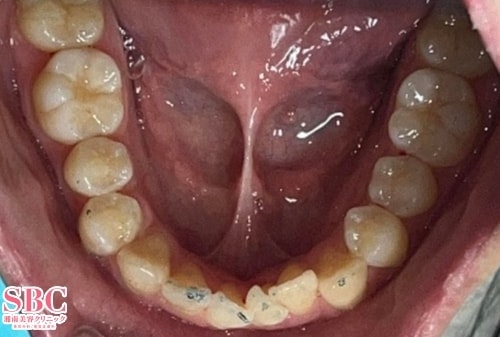

No.346562【美容歯科】インビザラインGOで前歯のガタツキを改善

施術前

前歯のガタツキがお悩みで、部分矯正で治療をご希望。

施術後7ヶ月後

約半年で並びが整いました。